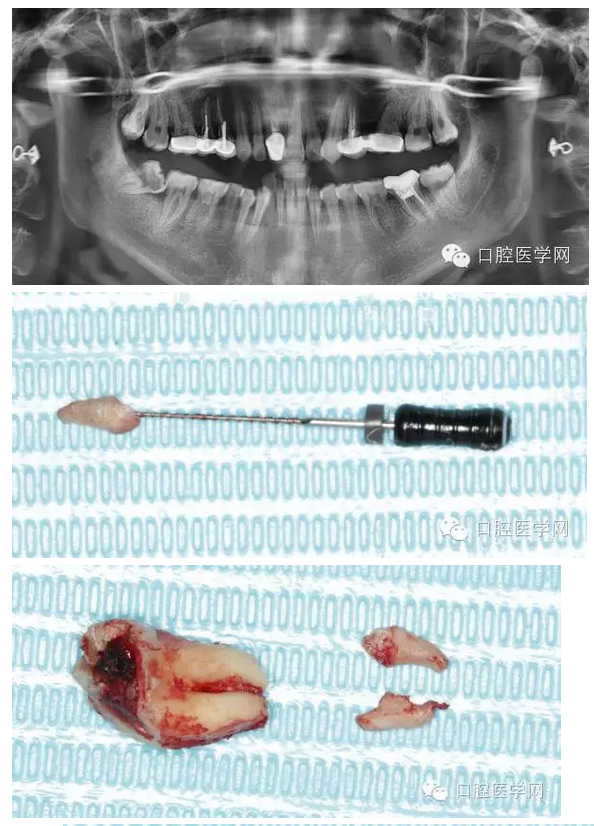

檢查發(fā)現(xiàn)右下8近中前傾阻生,合面大面積齲壞。拍全景片顯示右下8根尖向近中彎曲,右下7遠中有淺齲,遠中頸部有骨缺損。

拔牙過程就不贅述了,果然斷根了,于是用40號H銼插入牙根斷面的根管口里,并盡量擰緊,然后拔出。最近好像買不到碧藍麻,只有斯康杜尼,局部浸潤麻醉后出血明顯,嚴重影響操作,為了找根管口,擦拭了N個小棉球,讓人不堪忍受!讓人懷念的碧麻??!